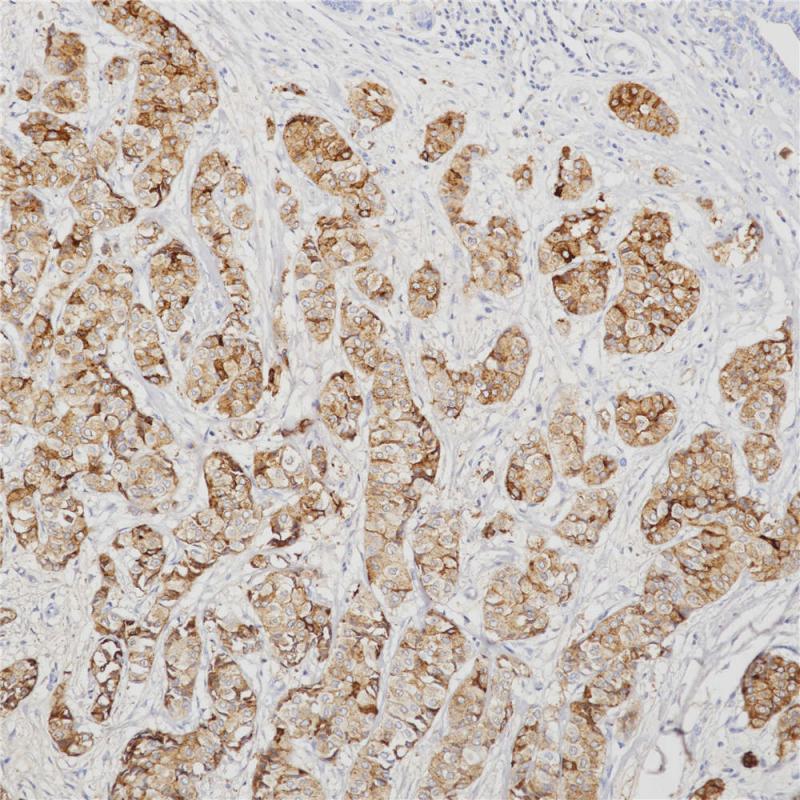

GCDFP-15即gross cystic disease fluid protein 15,是泌乳素诱导蛋白家族中的一员。GCDFP-15抗原可表达于非肿瘤性浆液性涎腺腺体、精囊和乳腺以及乳腺囊肿液等中,可作为乳腺癌标记物。该抗体主要用于乳腺癌的诊断,也常与mammaglobin 联用以判断乳腺癌微小病灶的转移情况。

阳性对照

乳腺癌